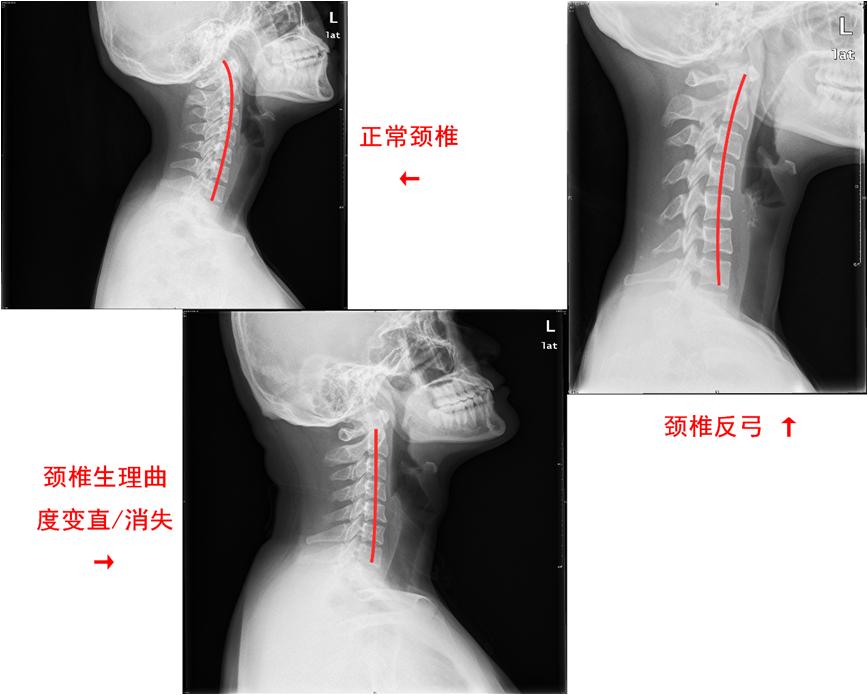

颈椎生理曲度变直/消失,通俗来讲就是脖子变直了,指的是在某些诱因(包括长期的不良姿势、外伤、感染、退变等)导致的颈椎原本向前凸出的弧度减小甚至消失,严重者甚至会出现颈椎反弓(形成向后凸出的弧度)(如图所示)。